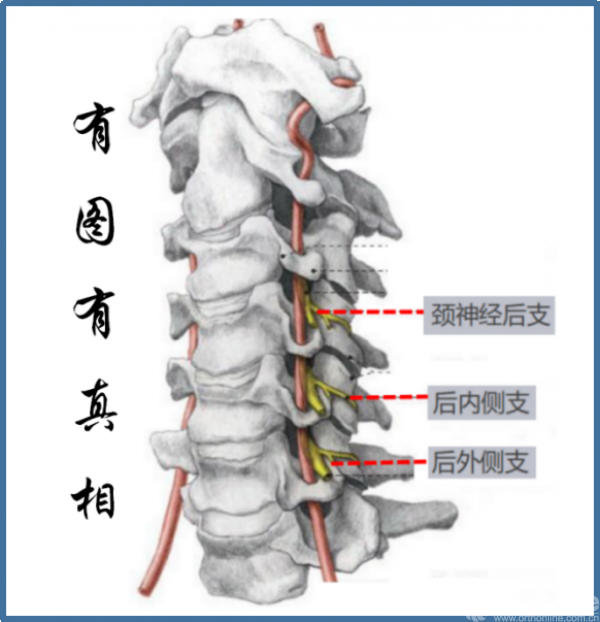

神经:

颈背部痛觉的传入纤维位于脊神经后支,其向后绕过关节突后分为外侧支和内侧支:

①内侧支发出后向棘突走行,分布于骨、关节、部分肌和皮肤。

②外侧支发出后则向后走行,多分布于肌肉,支配头长肌、头夹肌、头半棘肌、颈半棘肌及斜方肌等。

因颈神经后支距离上关节突尖部仅5.5~7.4mm,故颈椎后路手术显露关节突关节外侧关节囊时可能损伤脊神经后支,造成:

①内侧支损伤→相应皮节区疼痛和僵硬感

②外侧支损伤→所支配肌肉的失神经萎缩